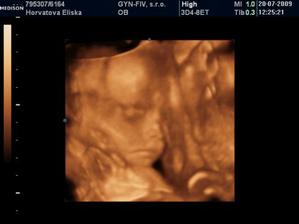

Dvojicky po KET

tak sme sa dockali-nase dvojicky sa narodili v 37+1 tt -20.10.09 cisarskym rezom -11:00 Matúško 3150g a 48cm a 11:02 Natálka 3030g 48cm,

v prvej poradni dvojtyzdnovi vazime uz 3560 a 3420g,

necele tri mesiace-vazime 6290g Matus 6190g Natalka, a to papame len MM!